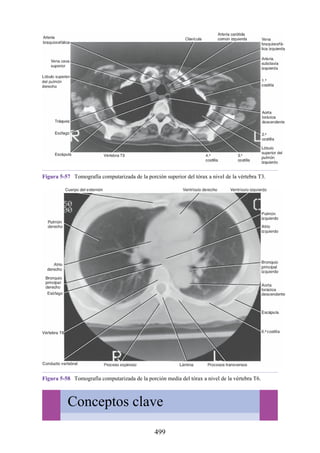

eleva el tono, pero no produce movimiento) para estabilizar el origen del motor

principal de modo que este pueda actuar con eficacia. Por ejemplo, los músculos